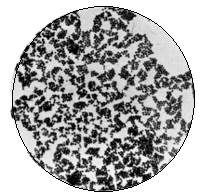

vi*Bacillus Tuberculosis | to face 280 |

*Bacillus Tuberculosis | 280 |

*Streptococcus Pyogenes | 280 |

*Bacillus Anthracis | 280 |